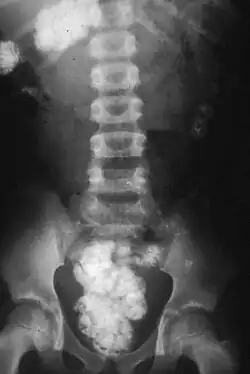

Silica in the soil that has been eaten by a woman shows up as white on this plain X-ray